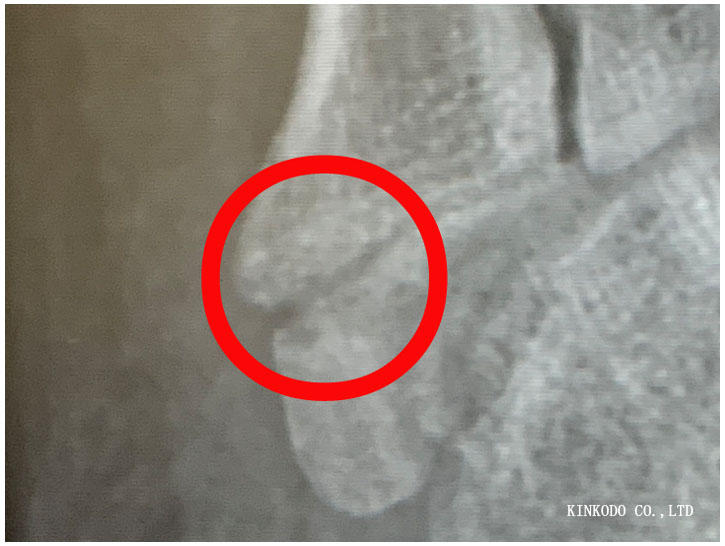

診察室に入ると既にレントゲン写真が先生の机の横にあり。先生来る前にスマホで。

どう変わっているのか?変わっていないのか?

まだなのか?どうなのか?

先生の説明によるとまだ骨折線は見えている。完全にくっつくにはまだ日にちがかかる。

と言われてももう走っているので、正直に先日400メートル×15本インターバルやってますけどと伝えました。

1月30日だったよね!(大阪ハーフ)と言われて、それでは安心の為にもその前にもう一度レントゲン撮っておくか?と言われて再度受診することになりました。

まだ完治じゃないのか・・・まあ走るけど。